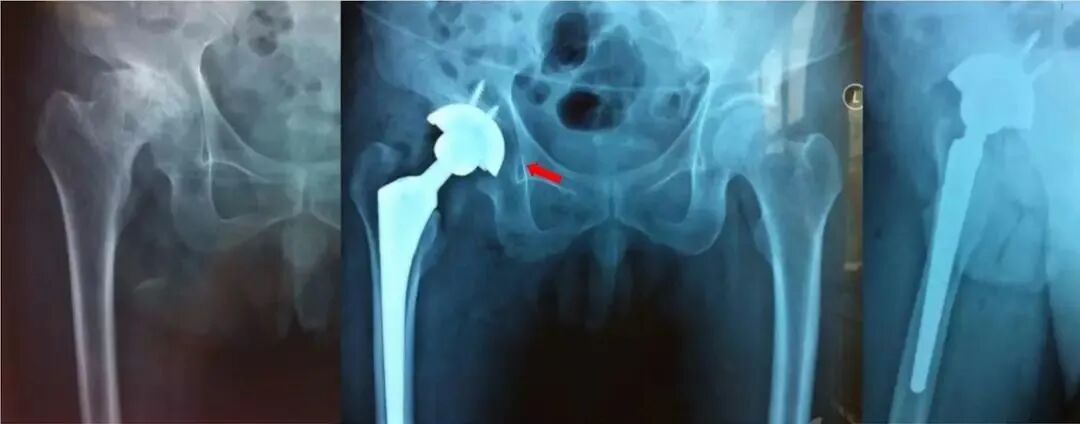

①旋转中心不佳:旋转中心上移外移,除了造成下肢短缩臀中肌无力外,也会早期假体松动。

②假体边缘出现透亮线:如果Ⅰ区和Ⅱ区出现透亮线则更糟糕,透亮线的存在往往是由于非同心圆磨挫导致的,影响骨长入,可能会引起早期松动。

③髋臼旋转中心外移

问题:旋转中心上移外移,没打在真臼上。

原因:可能没找到马蹄窝,横韧带,磨挫上移。